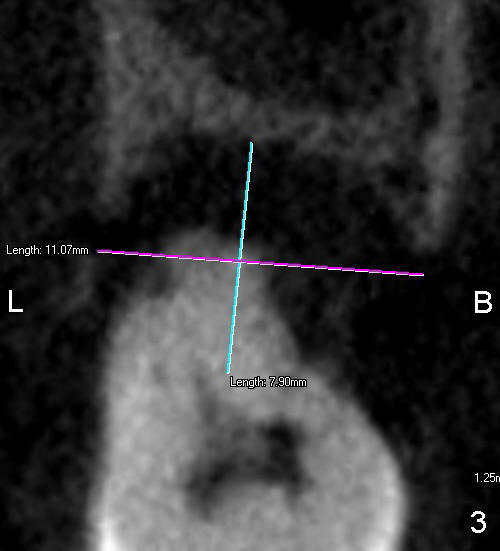

Measurement of the socket of #15 is done to determine the size of implant to be placed immediately after extraction. Fig.1 is a section showing the mesiodistal dimension of the 2nd molar, whereas Fig.2 and 3 are axial and coronal sections at the midroot level, respectively. Is 8x11 mm screw implant appropriate?